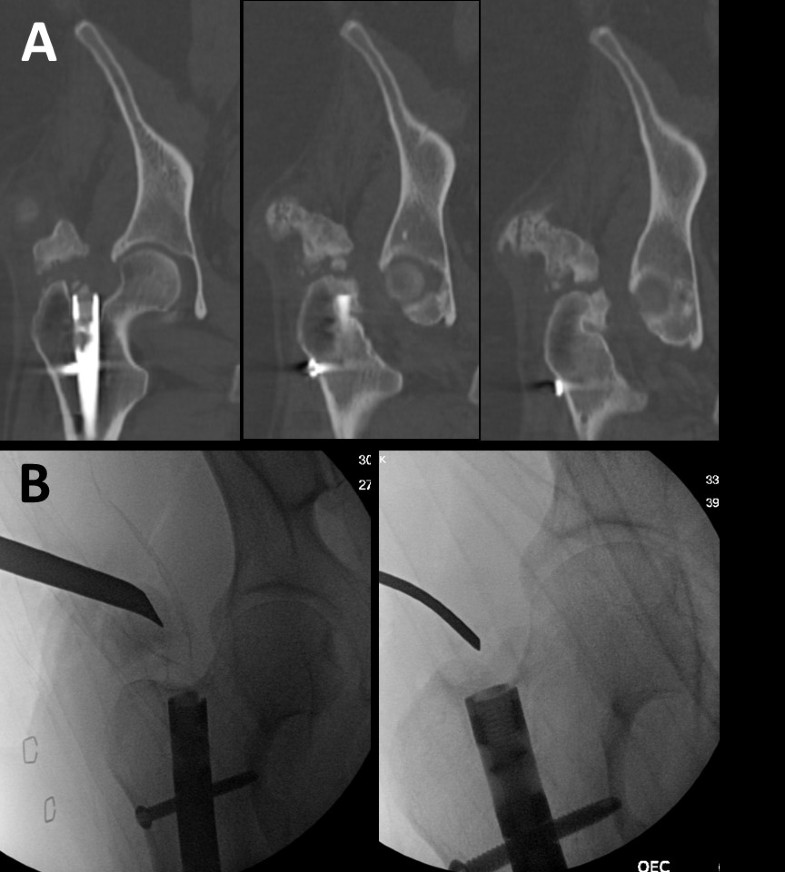

From www.semanticscholar.org

Figure 1 from An unpredictable complication of femoral reaming When What Is Femoral Reaming Table 1 shows the frequency distribution of age and sex of. Reaming results in elevated temperature and pressure within the intramedullary cavity, which may adversely affect bone healing. If the medullary canal is narrow, it may be necessary to enlarge it by reaming to allow the insertion of a larger diameter nail with sufficient strength. Femoral shaft fractures are a. What Is Femoral Reaming.

Figure 4 from An unpredictable complication of femoral reaming When What Is Femoral Reaming Ream close to endosteal cortex, which has strongest cancellous bone; In general, reamed nailing allows the use of larger diameter implants and may therefore provide greater. If the medullary canal is narrow, it may be necessary to enlarge it by reaming to allow the insertion of a larger diameter nail with sufficient strength. Femoral shaft fractures are a common orthopedic. What Is Femoral Reaming.